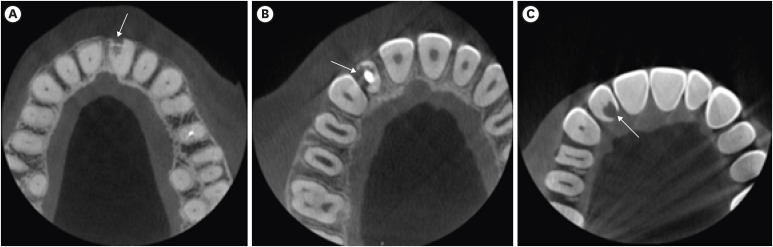

Subsequently, the scans with the presence of ECR were assessed under the same conditions and software used in the first step to characterize the cases. The cases were classified according to the 3D classification [12] (Figure 2). The height of the lesions was scored as (1) supracrestal, if it was located above the bone crest; (2) subcrestal, if it extended into the coronal third of the radicular dentin; (3) extending into the middle third of the radicular dentin; or (4) extending into the apical third of the radicular dentin. The circumference of the lesions was rated as smaller than 90o (A), between 90o and 180o (B), between 180o and 270o (C), or greater than 270o (D), considering the 360° extent of the root in the axial plane. The proximity of the lesions to the root canal was graded as within the dentin (d) or showing pulp involvement (p). To evaluate the height of the lesion, sagittal and coronal CBCT views were used. To evaluate lesion circumference and proximity to the root canal, the axial CBCT view corresponding to the largest dimension of ECR was used.

Figure 2

Examples of external cervical resorption indicated by white arrows. (A, B) Classification 1Ad. (C, D) classification 2Bd. (E, F) classification 3Ap. (G, H) classification 4Ap, according to the 3-dimensional classification.

The sample distribution according to the 3D classification, tooth type, and port of entry is exhibited in Table 4. The classification 4Dp was the most frequently found with 15 cases, followed by the classification 3Bp, with 12 cases. The least commonly found classifications were 1Ad, 1Bd, 1Bp, and 3Dp, with 1 case each. Considering only the height of the lesion, height 3 (mid-third of the root) was the most frequently found.

Taking into account the lesion height and circumferential spread, the most frequent classification in the present study was 3 (mid-third of the root) and more than 180°, respectively. Although Matny et al. [5], in 2020, did not use the 3D classification, strictly speaking, because the authors also used 2D radiographs, they classified the sample according to the height and circumferential spread in 3D examinations. It was found that most cases had reabsorption extending to the middle and apical thirds of the root and affecting more than 180° of the root, which corroborates our findings. In 2020, Jebril et al. [14] analyzed an ECR sample using the 3D classification and found a greater quantity (3 teeth) with the 2Bp classification. However, that study used a limited sample of 14 teeth. Because the clinical decision on the treatment plan and prognosis depends on the extent of the resorptive defect, class 4 of the Heithersay classification and height degree 4 of the 3D classification, which was the second more prevalent degree in the present study, suggest that the progress should be monitored until extraction of the tooth becomes inevitable as any interventionist approach is discouraged. According to Matny et al. [5], even in lesions classified as classes 1 or 2, the extent of the resorptive defect can reach 28% of the root surface, and lesions classified as class 4 reaches up to 58% loss of root structure. This point reinforces that an early diagnosis is essential for effective management and better prognosis, since an earlier diagnosis means that a greater percentage of healthy dental tissue is preserved, thereby increasing the chances of successful treatment.